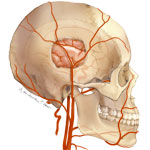

- Aneurysm clipping

Clipping is a surgery performed to treat an aneurysm - a balloon-like bulge or weakening of an artery wall. As an aneurysm grows, it can become so thin that it leaks or ruptures, releasing blood into the spaces around the brain. This bleeding is life threatening. A neurosurgeon opens the skull (craniotomy) and places a tiny clip across the neck of the aneurysm to stop or prevent an aneurysm from bleeding.

- Craniotomy

Craniotomy is a surgery to cut a bony opening in the skull. A section of the skull, called a bone flap, is removed to access the brain underneath. A craniotomy may be small or large depending on the problem. It may be performed to treat tumors, hematomas, aneurysms, AVMs, skull fractures, foreign objects, swelling of the brain, or infection. The bone flap is usually replaced with tiny plates and screws.